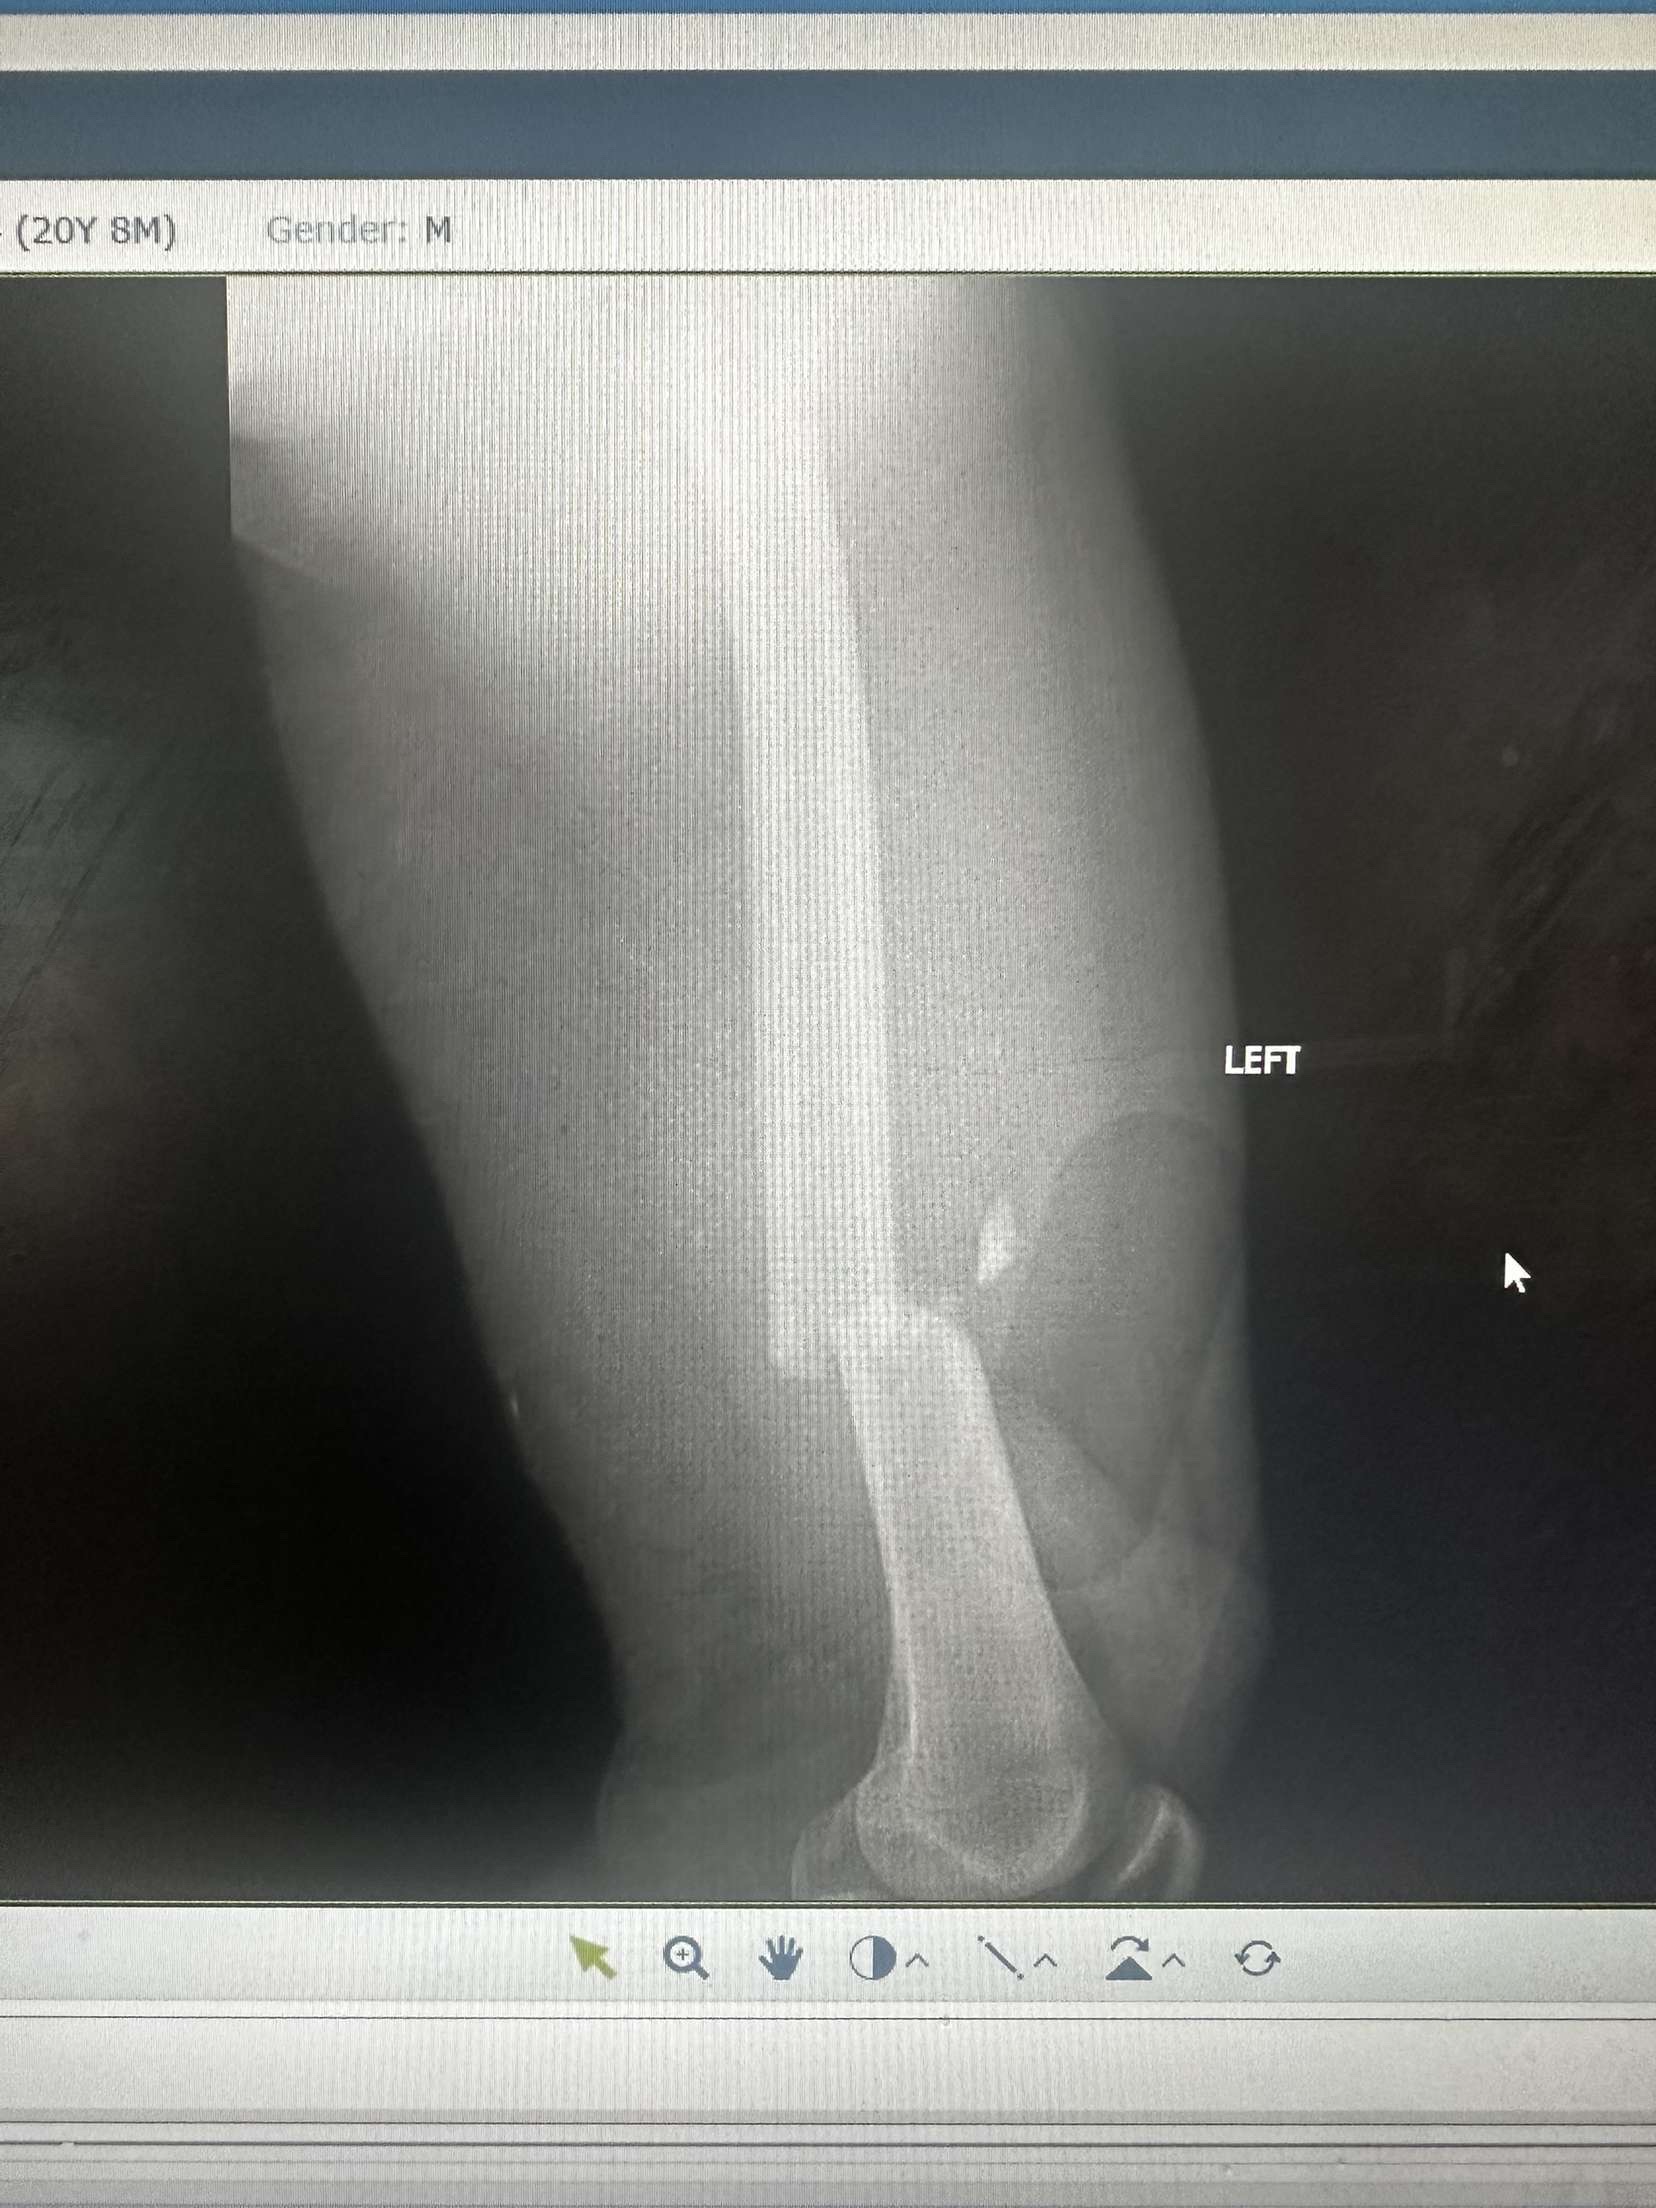

He broke his femur and tore femoral artery he also has a collapsed lung and surgery on his femur on Wednesday.